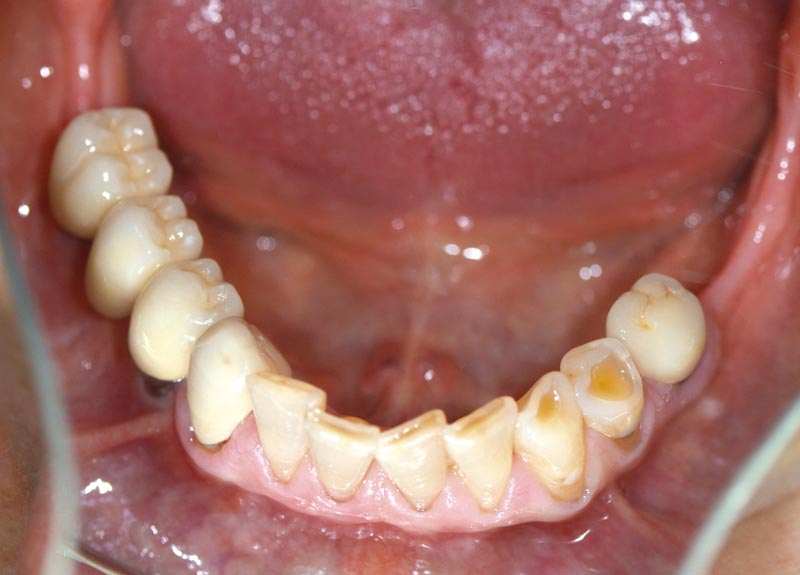

14/14 - Final clinical situation with prosthetics 18 months post augmentation